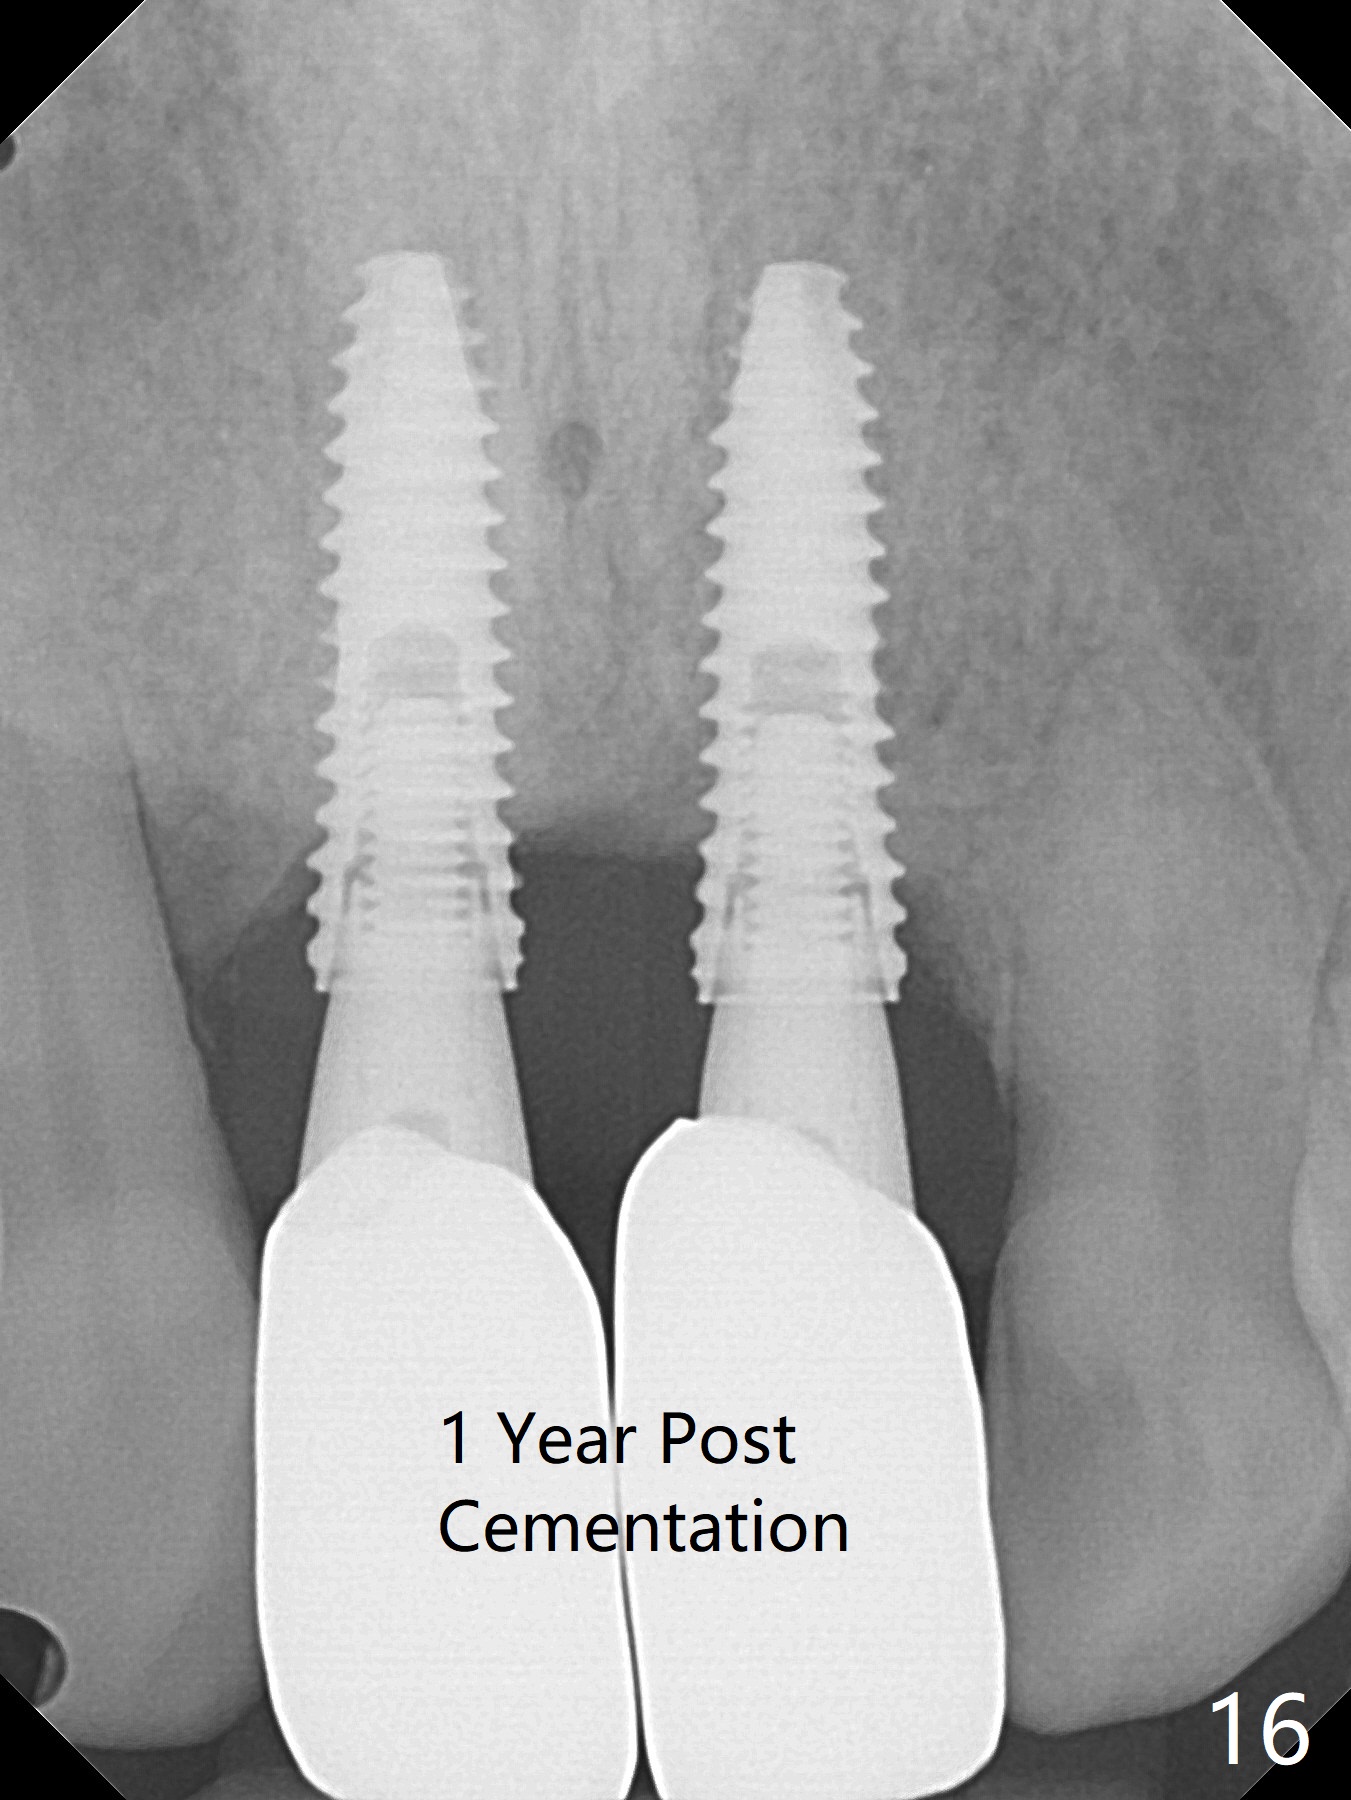

The gingiva remains recessive at #8 and 9 six months post immediate implant placement with bone graft (Fig.1). The buccal plate at #8 is particularly concave before (Fig.2 *) and after (Fig.3) abutment removal. The bony defect repair is assisted by placing a 4 mm tenting screw between the 2 implants (Fig.4) and placing allograft mixed with PRF (as putty) around the screw (Fig.5 (after replacement of the abutments)). The buccal contour improves because of the tenting screw and the bone graft placement (Fig.6 (as well as PRF and 6-month membranes)). The wound dehisces 12 days postop and immediately before leaving country for months (Fig.7). The sutures are removed, Osteogen plug is inserted (Fig.8) and periodontal dressing is applied (Fig.9). PA is taken to show the tenting screw (Fig.10 T). The latter is exposed 3 months postop (Fig.11,12). It appears that gingival graft is a must (Fig.13). Make a palatal stent, remove the temp with abutments and create a bleeding surface before harvesting a large piece of tissue. Connective tissue graft is done 5 months post bone graft (Fig.14). In fact there is no implant thread exposure. In fact the connective tissue graft does not survive. The abutments are re-prepared for pink porcelain (Fig.15). The bone loss is stable 1 year post cementation in spite of incomplete abutment seating (Fig.16). The soft tissue is nearly normal (Fig.17).